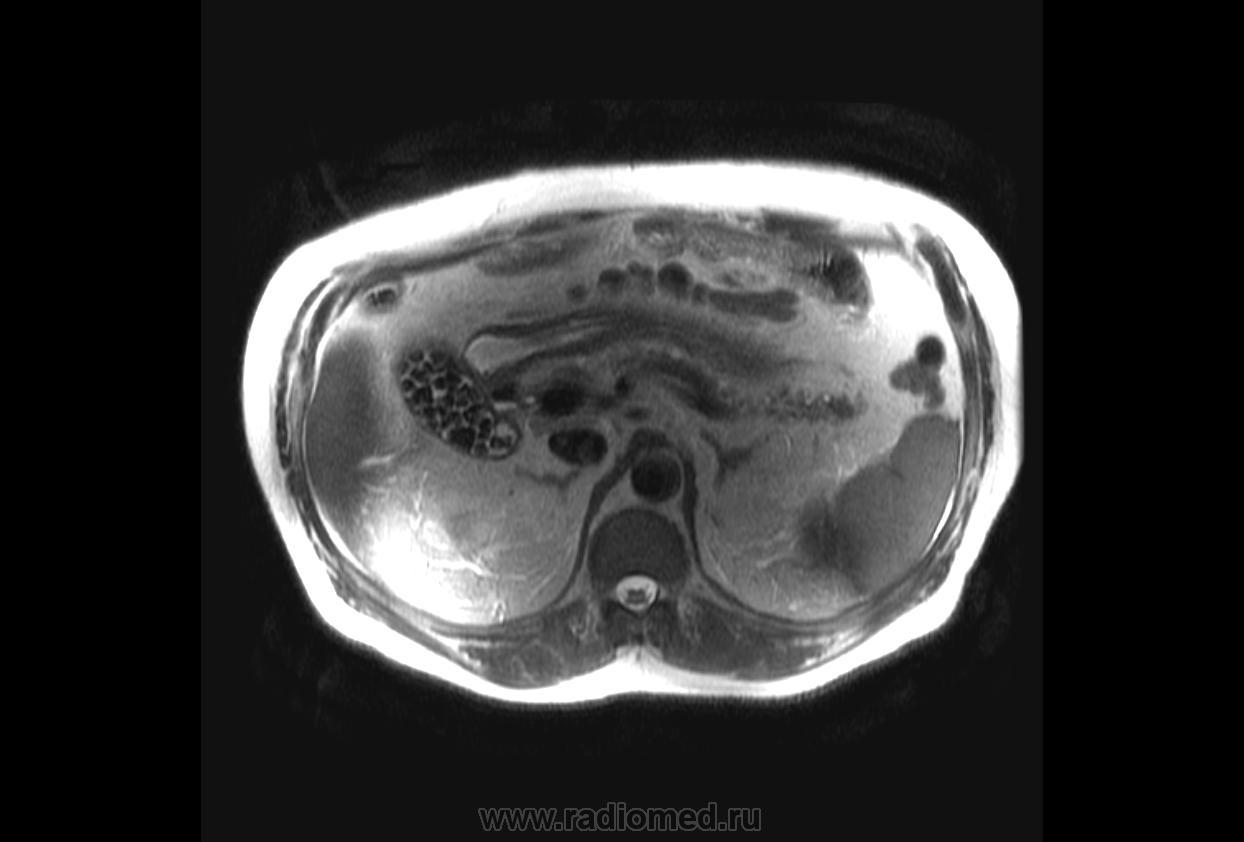

Пациентка 27 лет. Поступила в госпиталь с предыдущего этапа оказания медицинской помощи с диагнозом направления "механическая желтуха. Камень правого печеночного протока". Желтая, как канарейка. Но живот практически безболезный. Небольшое чувство тяжести в правом подреберье. Проведено повторное УЗИ. Данных за билиарную гипертензию не выявлено. Зато получено вот такое изображение желчного пузыря. Внутренние структуры пузыря практически не отличаются от стенки желчного пузыря.

Изображение